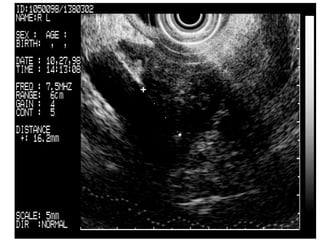

Rectal ca

A large perirectal mass is seen invading the rectal wall. FNA biopsy (Pentax FG-32UA) of the mass confirmed recurrence of prostatic cancer (inset).